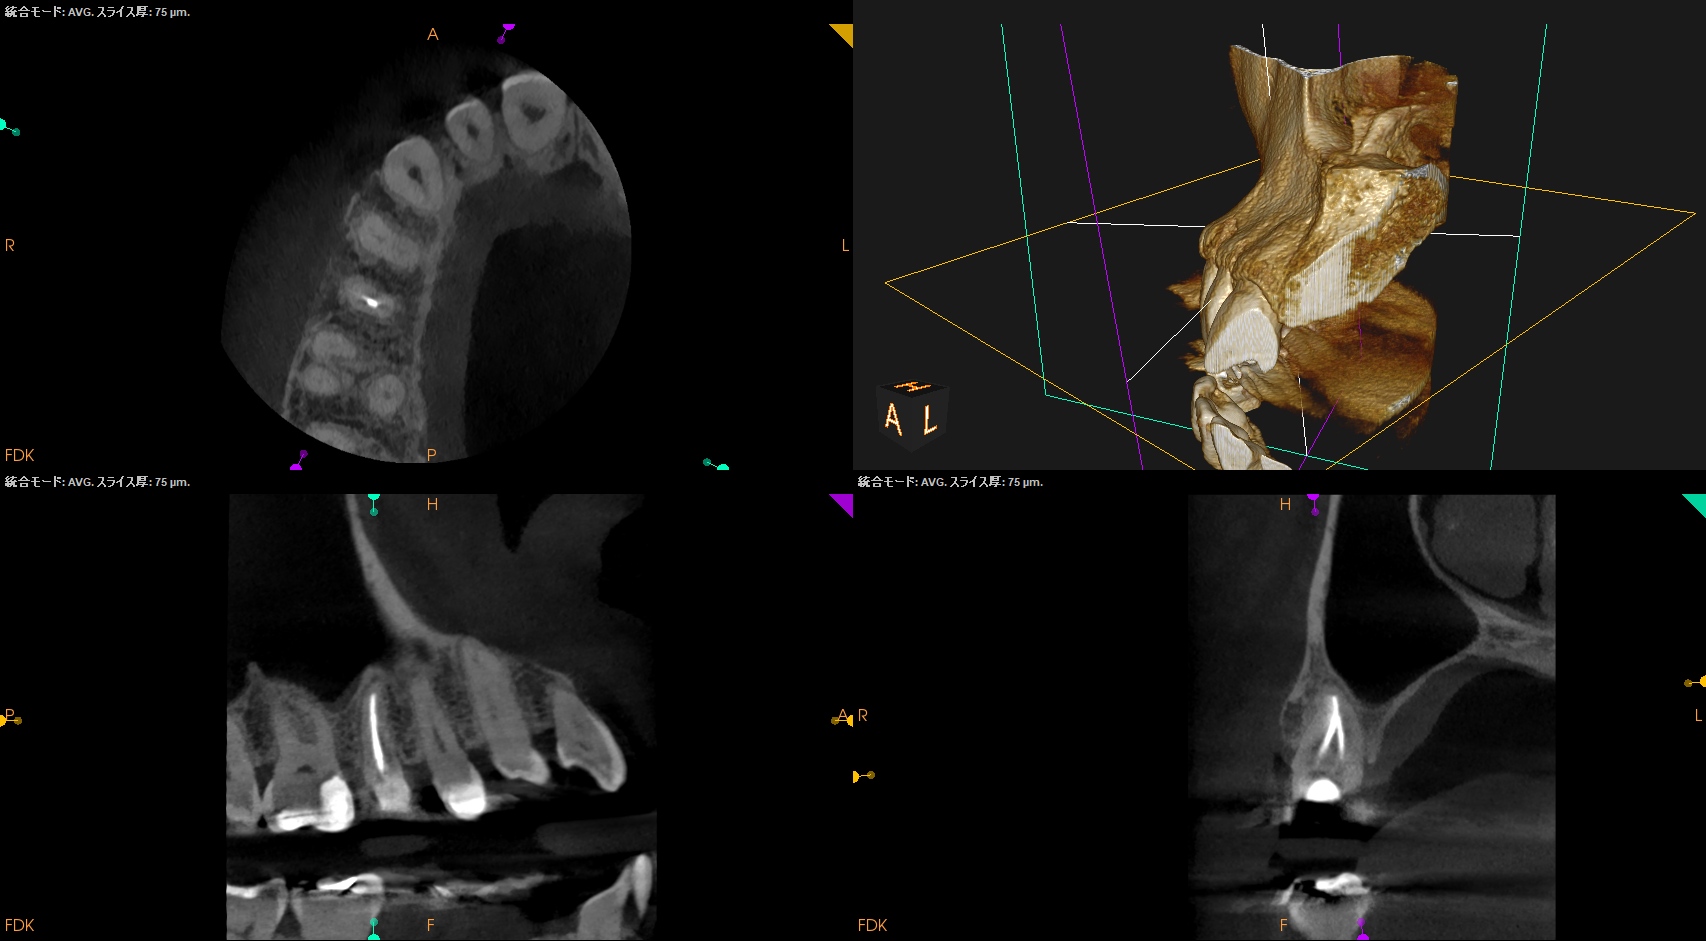

病変のない、Initial RCTだ。

Pulp Dx: Asymptomatic irreversible pulpitis

Periapical Dx: Symptomatic apical periodontitis

Recommended Tx: RCT

術後にPA, CBCTを撮影した。